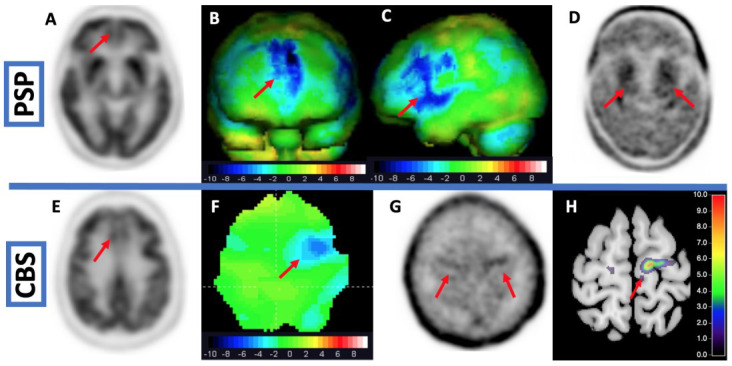

In a cross-sectional study using 18F-PI-2620 [ref. 174], patients with PSP were compared to patients with PD and MSA and healthy controls. Additionally, the authors performed 18F-PI-2620 in vitro autoradiography in four PSP cases that were independent of the in vivo cohort. The in vitro analyses revealed a blockable 18F-PI-2620 binding in the basal ganglia and the frontal cortex that was colocalized to AT8-positive aggregated tau. In vivo, patients with PSP showed significantly higher tracer binding in the pallidum and the nucleus subthalamicus than healthy controls. Binding in cortical regions could not differentiate between PSP and controls and there was no correlation between symptom severity and 18F-PI-2620 binding. The analyses at the single patient level revealed a sensitivity of 80% for PSP-RS and 55% for PSP-non-RS at a specificity of 83%. It should be elucidated that a cortical 18F-PI-2620 binding could be assessed in vitro but astonishingly there were no differences in cortical binding between PSP and controls in vivo. An autoradiographic study shed further light on the binding properties of 18F-PI-2620 to PSP tau in vitro [ref. 175]. Therefore, the authors compared the autoradiographic binding of 18F-PI-2620 in PSP, AD, and healthy controls for formalin-fixed paraffin-embedded (FFPE) and frozen tissue with immunohistochemical AT8 staining. Interestingly in FFPE samples, autoradiographic and immunohistochemical tau load correlated significantly in PSP and AD, whereas in frozen tissue this correlation was only existing in AD. The binding ratios in PSP in FFPE were significantly lower than those in AD, the authors explain this with the lower tau load in PSP compared to AD and to different binding affinities in 4R- and 3R/4R-tauopathies [ref. 175]. In a study with micro autoradiography, 3H-PI-2620 signal (silver grains) correlated with immunohistochemical staining with an antibody for tau (MCH1) [ref. 176]. Therefore, Willroider et al. draw the conclusion that an FFPE-induced off-target source is unlikely and that the 4R-tau might be less preserved in frozen tissue [ref. 175]. In a neuropathological study examining AT8-staining in a patient with CBD who died two weeks after a PET scan with 18F-PI-2620, the PET signal did not correlate with the AT8-staining [ref. 177]. Figure 4 (top row) shows PET imaging of a patient with probable PSP. The prior FDG-PET was not distinct for PSP. The additional tau PET with 18F-PI2620 revealed tau depositions in the basal ganglia.

In this context, Song et al. examined whether the binding characteristics of 18F-PI-2620 could differentiate between 3R/4R- and 4R-tauopathies by non-invasive reference tissue modeling [ref. 179]. Song et al. found that there was a higher delivery and efflux of 18F-PI-2620 in cortical but not in subcortical regions in 4R- as compared to 3R/4R-tauopathy. The DVR of 18F-PI-2620 was significantly higher in 3R/4R. The authors draw the conclusion that the tracer binds less stable to 4R-tau. A reason for this could be different configurations of tracer binding pockets of tau aggregates. In this context, it is worth mentioning a computational study by Zhou et al. They could demonstrate in silico that none of the second-generation tracers is selective to 4R tau. The authors conclude that computational modeling of tracer binding characteristics can help to develop new and highly selective 4R tracers [ref. 180]. Figure 4 (bottom row) shows PET imaging from a patient with CBS. The FDG-PET showed hypometabolism in the left precentral gyrus. The scan with 18F-PI2620 revealed tau depositions in this area.